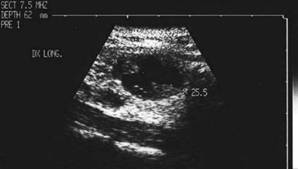

Femeie de 74 ani. Carcinom anaplazic voluminos in lobul

drept.

La examenul eco cu sonda convexa de 5.0 MHz leziunea pare benigna